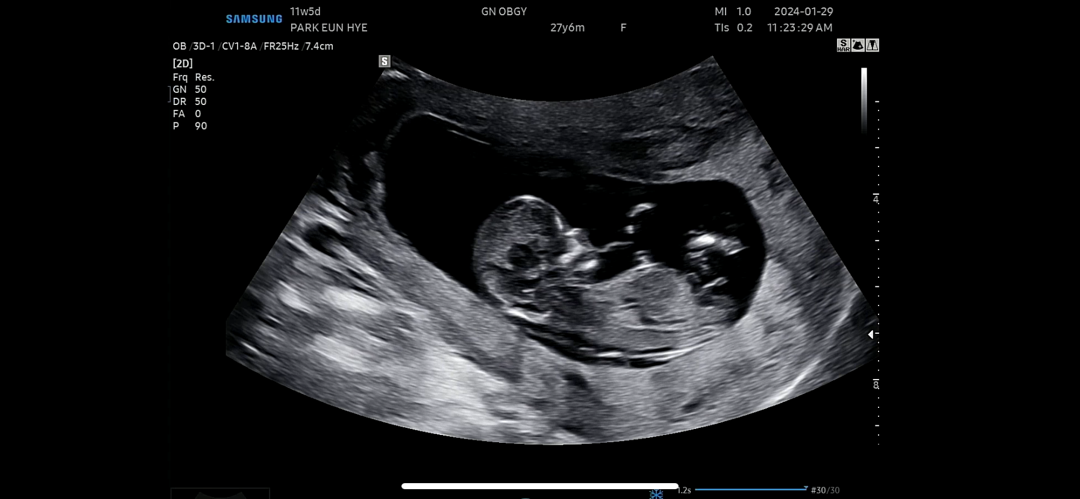

12주 각도법 고수님들!!!!

각도법좀 봐주십셔!!!!!!!🐥🐥🐥

각도로봐선 아들인데 끝이 갈라져있는게 딸같기도하고 긴가민가하네요 아들은 뭉툭해야하거든요